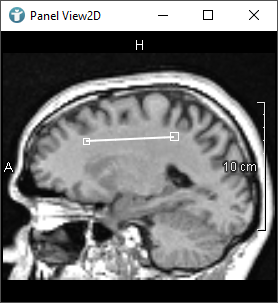

The following images show editors available in MeVisLab for drawing CSOs:

The SoCSOIsoEditor and SoCSOLiveWireEditor are special, because they are using an algorithm to detect edges themselves.